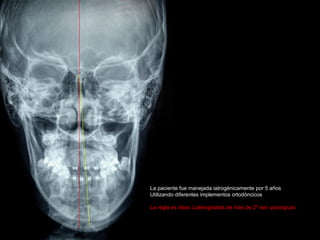

La paciente fue manejada iatrogénicamente por 5 años

Utilizando diferentes implementos ortodóncicos

La regla es clara: Laterognatias de más de 2º son quirúrgicas

La paciente fuemanejada iatrogénicamente por 5 años Utilizando diferentes implementos ortodóncicos La regla es clara: Laterognatias de más de 2º son quirúrgicas